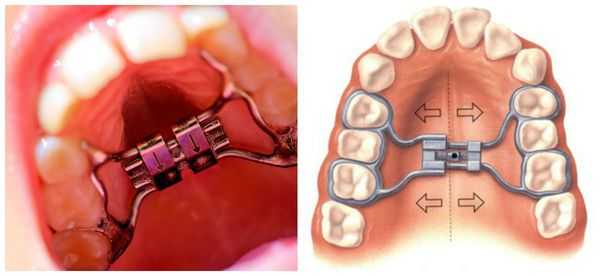

Для исправления прикуса используют съёмные и несъёмные ортодонтические пластинки из пластмассы с различными видами крепления (кламмеры, минивинты, ортодонтические кольца и коронки), а также другие конструкции с активными элементами (винтами и пружинами). Такие аппараты могут быть одночелюстными, двучелюстными и одночелюстными с межчелюстным действием.

Самая распространённая ортодонтическая аппаратура для исправления прикуса — брекет-системы. Для этого используются различные дополнительные приспособления: кнопки и крючки, эластики и эластичные цепочки.

Срок лечения брекет-системами в среднем составляет 15-18 месяцев и проводится в обязательном порядке на двух челюстях с последующим ношением ретейнера (шины) не менее 1,5 сроков активного периода лечения.

Во время лечения к основные ортодонтические конструкции могут дополняться минивинтами. Чаще они применяются у взрослых пациентов для более стабильной опоры и прогнозируемого результата.

- аппарат Энгля для расширения/сужения челюстной дуги. Дуга конструкции требует периодической корректировки для уточнения ее давления с лингвальной стороны. Другие аппараты для быстрого небного расширения, небные эспандеры.